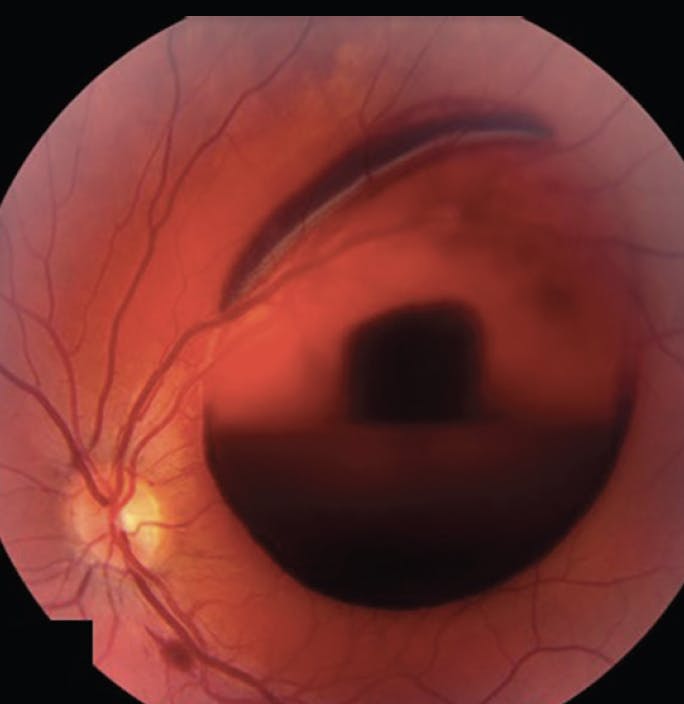

Examination of the posterior segment demonstrated a normal right eye, while the left eye had slightly tortuous vessels, a large preretinal/sub-internal limiting membrane (ILM) hemorrhage, a superior subretinal hemorrhage, and a flame-shaped retinal hemorrhage along the inferior arcade (Figure 1). Fluorescein angiography demonstrated normal arterial and venous filling times, without evidence of leakage. No macroaneurysm was identified.

<p>Figure 1. On fundus photography, the left eye demonstrated slight venous tortuosity, a large preretinal/sub-ILM hemorrhage, a superior subretinal hemorrhage, and a small flame-shaped hemorrhage along the inferotemporal arcade.</p>

Figure 1. On fundus photography, the left eye demonstrated slight venous tortuosity, a large preretinal/sub-ILM hemorrhage, a superior subretinal hemorrhage, and a small flame-shaped hemorrhage along the inferotemporal arcade.